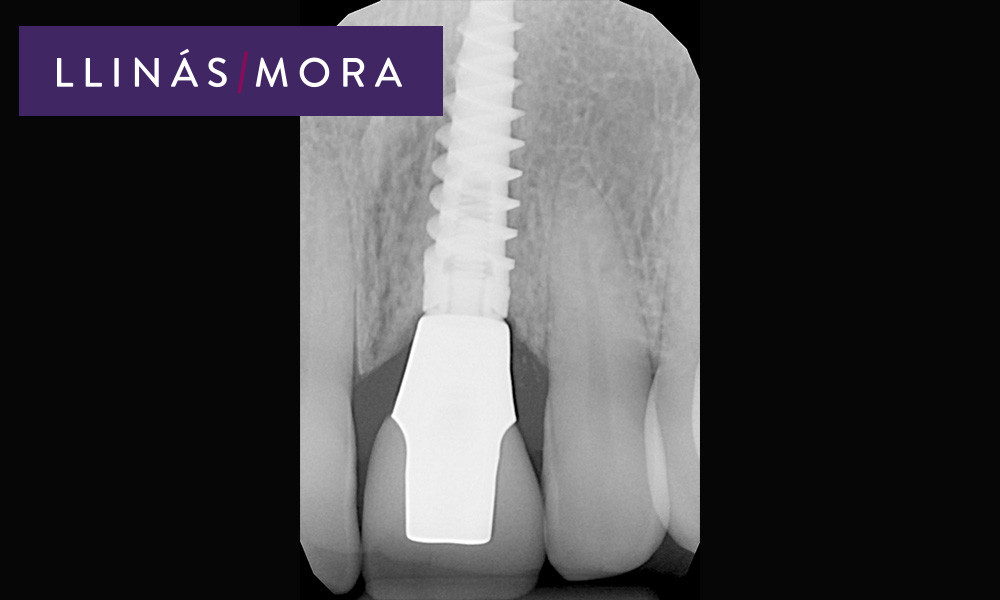

8. Radiografía del Implante